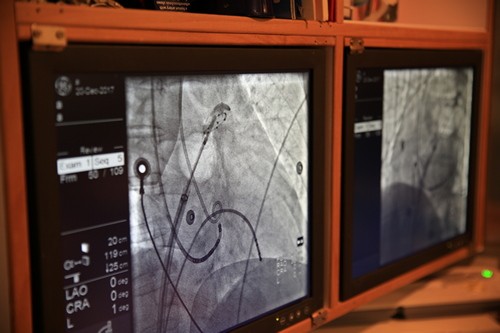

圖說:在美國經驗豐富的Dr. Wilber Su的指導下,謝仁哲醫師、蔡文欽醫師、張懷仁醫師分別為三位心房顫動的病人,進行心房肺靜脈冷凍氣囊消融術。